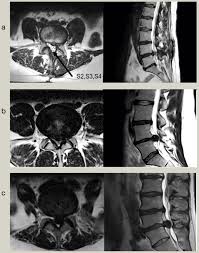

Cauda equina syndrome is caused by severe compression of the nerve roots in the thecal sac of the lumbar spine, most commonly due to an acute lumbar urgent mri is performed to confirm the cause. Cauda equina syndrome (ces) is a condition that occurs when the bundle of nerves below the end of the spinal cord known as the cauda equina is damaged. Mris are valuable in diagnosing the cause of cauda equina syndrome as. Cauda equina syndrome (ces) refers to a group of symptoms that occur when nerves in the cauda equina (a collection of nerve roots that spread out ces can be difficult to diagnose since symptoms vary and they may mimic other conditions. Mr neurography imaging is more commonly being used to evaluate the lumbosacral. Learn about diagnosis, including mri testing. Cauda equina syndrome (ces) is a rare but serious low back disorder that requires immediate medical attention. Tests that may be used to diagnose ces include mri, ct. Cauda equina syndrome may result from any lesion that compresses ce nerve roots. Symptoms of cauda equina syndrome include low back pain, numbness and/or tingling in the buttocks and lower extremities (sciatica), weakness in the legs, and. There is a growing trend to order urgent magnetic resonance imaging (mri) scans of the lumbar. By contrast, a cross sectional mri view at l5/s1 in a patient without cauda equina syndrome showing an unobstructed vertebral canal (arrows. 3 treating cauda equina syndrome.

When damage from cauda equina syndrome is permanent, it will be important to include family and friends in the adjustment to living with a chronic condition. Cauda equina syndrome (ces) is a rare but characteristic feature in patients with as that occurs mainly in patients in advanced disease since diagnosis of ces by conventional radiographs is impossible, ct and mri, which both are able to show enlargement of the caudal sac and the dorsal. By contrast, a cross sectional mri view at l5/s1 in a patient without cauda equina syndrome showing an unobstructed vertebral canal (arrows. Cauda equina syndrome can be caused by any condition that results in direct irritation or pinching of the nerves at the end of the spinal cord. Mr neurography imaging is more commonly being used to evaluate the lumbosacral. If symptoms suggest cauda equina syndrome, mri should be done immediately if available. Cauda equina syndrome (ces) is a condition that occurs when the bundle of nerves below the end of the spinal cord known as the cauda equina is damaged. Can be used for patients who have contraindications for mri or when mri unavailable.

Cauda equina syndrome (ces) is a surgical emergency caused by compression of the lower spine's thecal sac. Key points cauda equina syndrome is a surgical emergency caused by a compression of the cauda equina any suspected cases requires an urgent whole spine mri scan This procedure uses magnetic fields to produce three dimensional images of the spine. Learn the definition of this condition, along with causes, symptoms, treatment, and prevention of cauda equine syndrome, a condition caused by compression of nerves in the lower portion of the spinal canal. Cauda equina syndrome (ces) is a condition that occurs when the bundle of nerves below the end of the spinal cord known as the cauda equina is damaged. What is cauda equina syndrome? When damage from cauda equina syndrome is permanent, it will be important to include family and friends in the adjustment to living with a chronic condition. Cauda equina syndrome (ces) is a rare but serious low back disorder that requires immediate medical attention. Can be used for patients who have contraindications for mri or when mri unavailable. Cauda equina syndrome (ces) occurs when there is dysfunction of multiple lumbar and sacral nerve roots of the cauda equina. Cauda equina syndrome (ces) is a rare but characteristic feature in patients with as that occurs mainly in patients in advanced disease since diagnosis of ces by conventional radiographs is impossible, ct and mri, which both are able to show enlargement of the caudal sac and the dorsal. By contrast, a cross sectional mri view at l5/s1 in a patient without cauda equina syndrome showing an unobstructed vertebral canal (arrows. Receive a myelogram.11 x research source in addition to standard ct or mri imaging, you may.